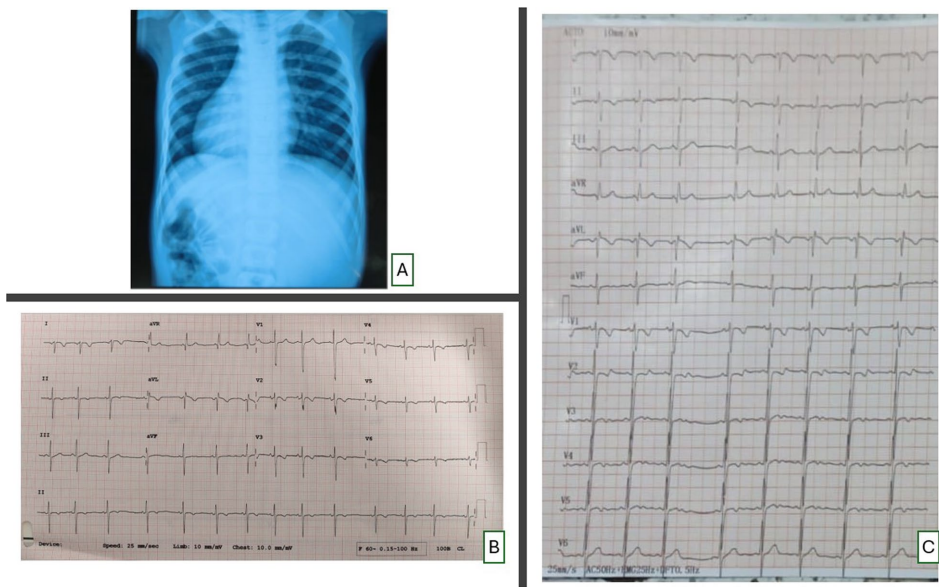

背景特征:患儿表现为发育迟缓(体重16kg)和活动后呼吸困难,听诊发现4/6级全收缩期杂音。心电图显示I、aVL导联P-T波倒置,aVR导联直立,符合典型镜像右位心特征。

影像学评估:胸片证实心脏右位伴肺血增多(CTR=0.67)。超声显示隧道型膜周部VSD(直径5-7mm),分流峰速70mmHg,距主动脉瓣3mm,最佳观察视角为右胸骨旁短轴2点钟位置(常规解剖的10点钟镜像位点)。